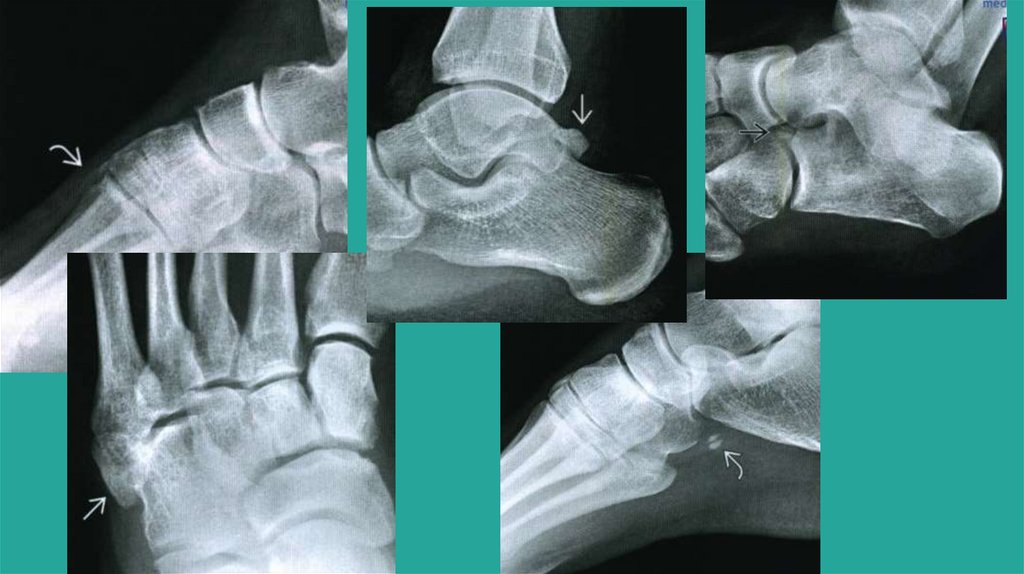

Многоугольные кости

Os supranaviculare, supratali

Os calcaneus secundarium

Os cuboideus secundarium

Os sustentaculum

Os talus accesorius

Рентгенограмма, КТ, МРТ добавочных костей голеностопного сустава и стопы